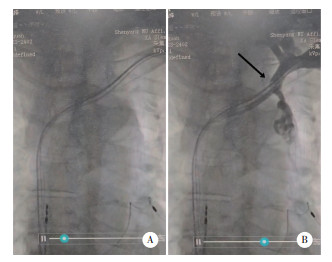

术前测试右心房及右心室参数正常,左心室阈值较高(2.5 V),术中穿刺左锁骨下静脉,导丝不能顺利到达SVC,遂造影发现患者SVC完全阻塞(图 3),见少许侧支循环。尝试更换PTCA导丝,仍不能顺利通过。分析SVC阻塞病因,结合已完成的辅助检查,可除外恶性疾病,可能与起搏器植入有关。考虑患者起搏器植入术后心功能获益大,结合患者病史及SVC血管情况,若行起搏器导线拔除(transvenous lead extraction,TLE)术或经皮静脉介入治疗,患者的远期预后无法预料,故选择姑息治疗。遂复测左心室双极和单极阈值,确定合理的项量,连接起搏器后测试阈值参数在合理范围内。仅行脉冲发生器置换术,将3根电极尾端连接脉冲发生器,术中测试提示各电极起搏参数良好。患者平卧位仍可见头颈部肿胀,但无双上肢肿胀,较2年前有所缓解。患者术后安全返回病房,无不适主诉,观察起搏器囊袋无出血、破溃及渗出。嘱患者卧床24 h,给予沙袋压迫切口6 h,术后24 h换药1次,然后每隔2~3 d换药1次,7 d后观察切口愈合良好,拆线,在超声优化下行起搏器程控,起搏器工作稳定后出院。出院后继续抗心力衰竭治疗。患者于术后1个月再次来我院行起搏器程控,各项参数良好,工作稳定。后续1年内每3个月进行1次程控,1年后改为每年进行1次程控。

| A,推入造影剂前;B,推入造影剂后. 黑色箭头为SVC完全阻塞,造影剂无法通过. 图 3 SVC造影结果 |